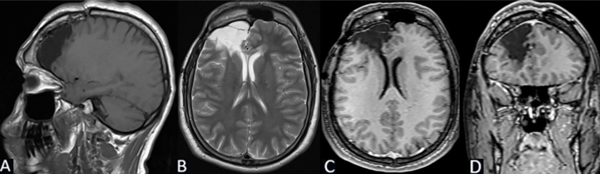

Se puede observar en la Figura 6 la RM postquirúrgica de cerebro.

Figura 6. Caso 1: RM de cerebro postquirúrgica. A) Secuencia T1, corte sagital. B) Secuencia T2, corte axial. C) Secuencia T1 con contraste, corte axial. D) Secuencia T1 con contraste, corte coronal.